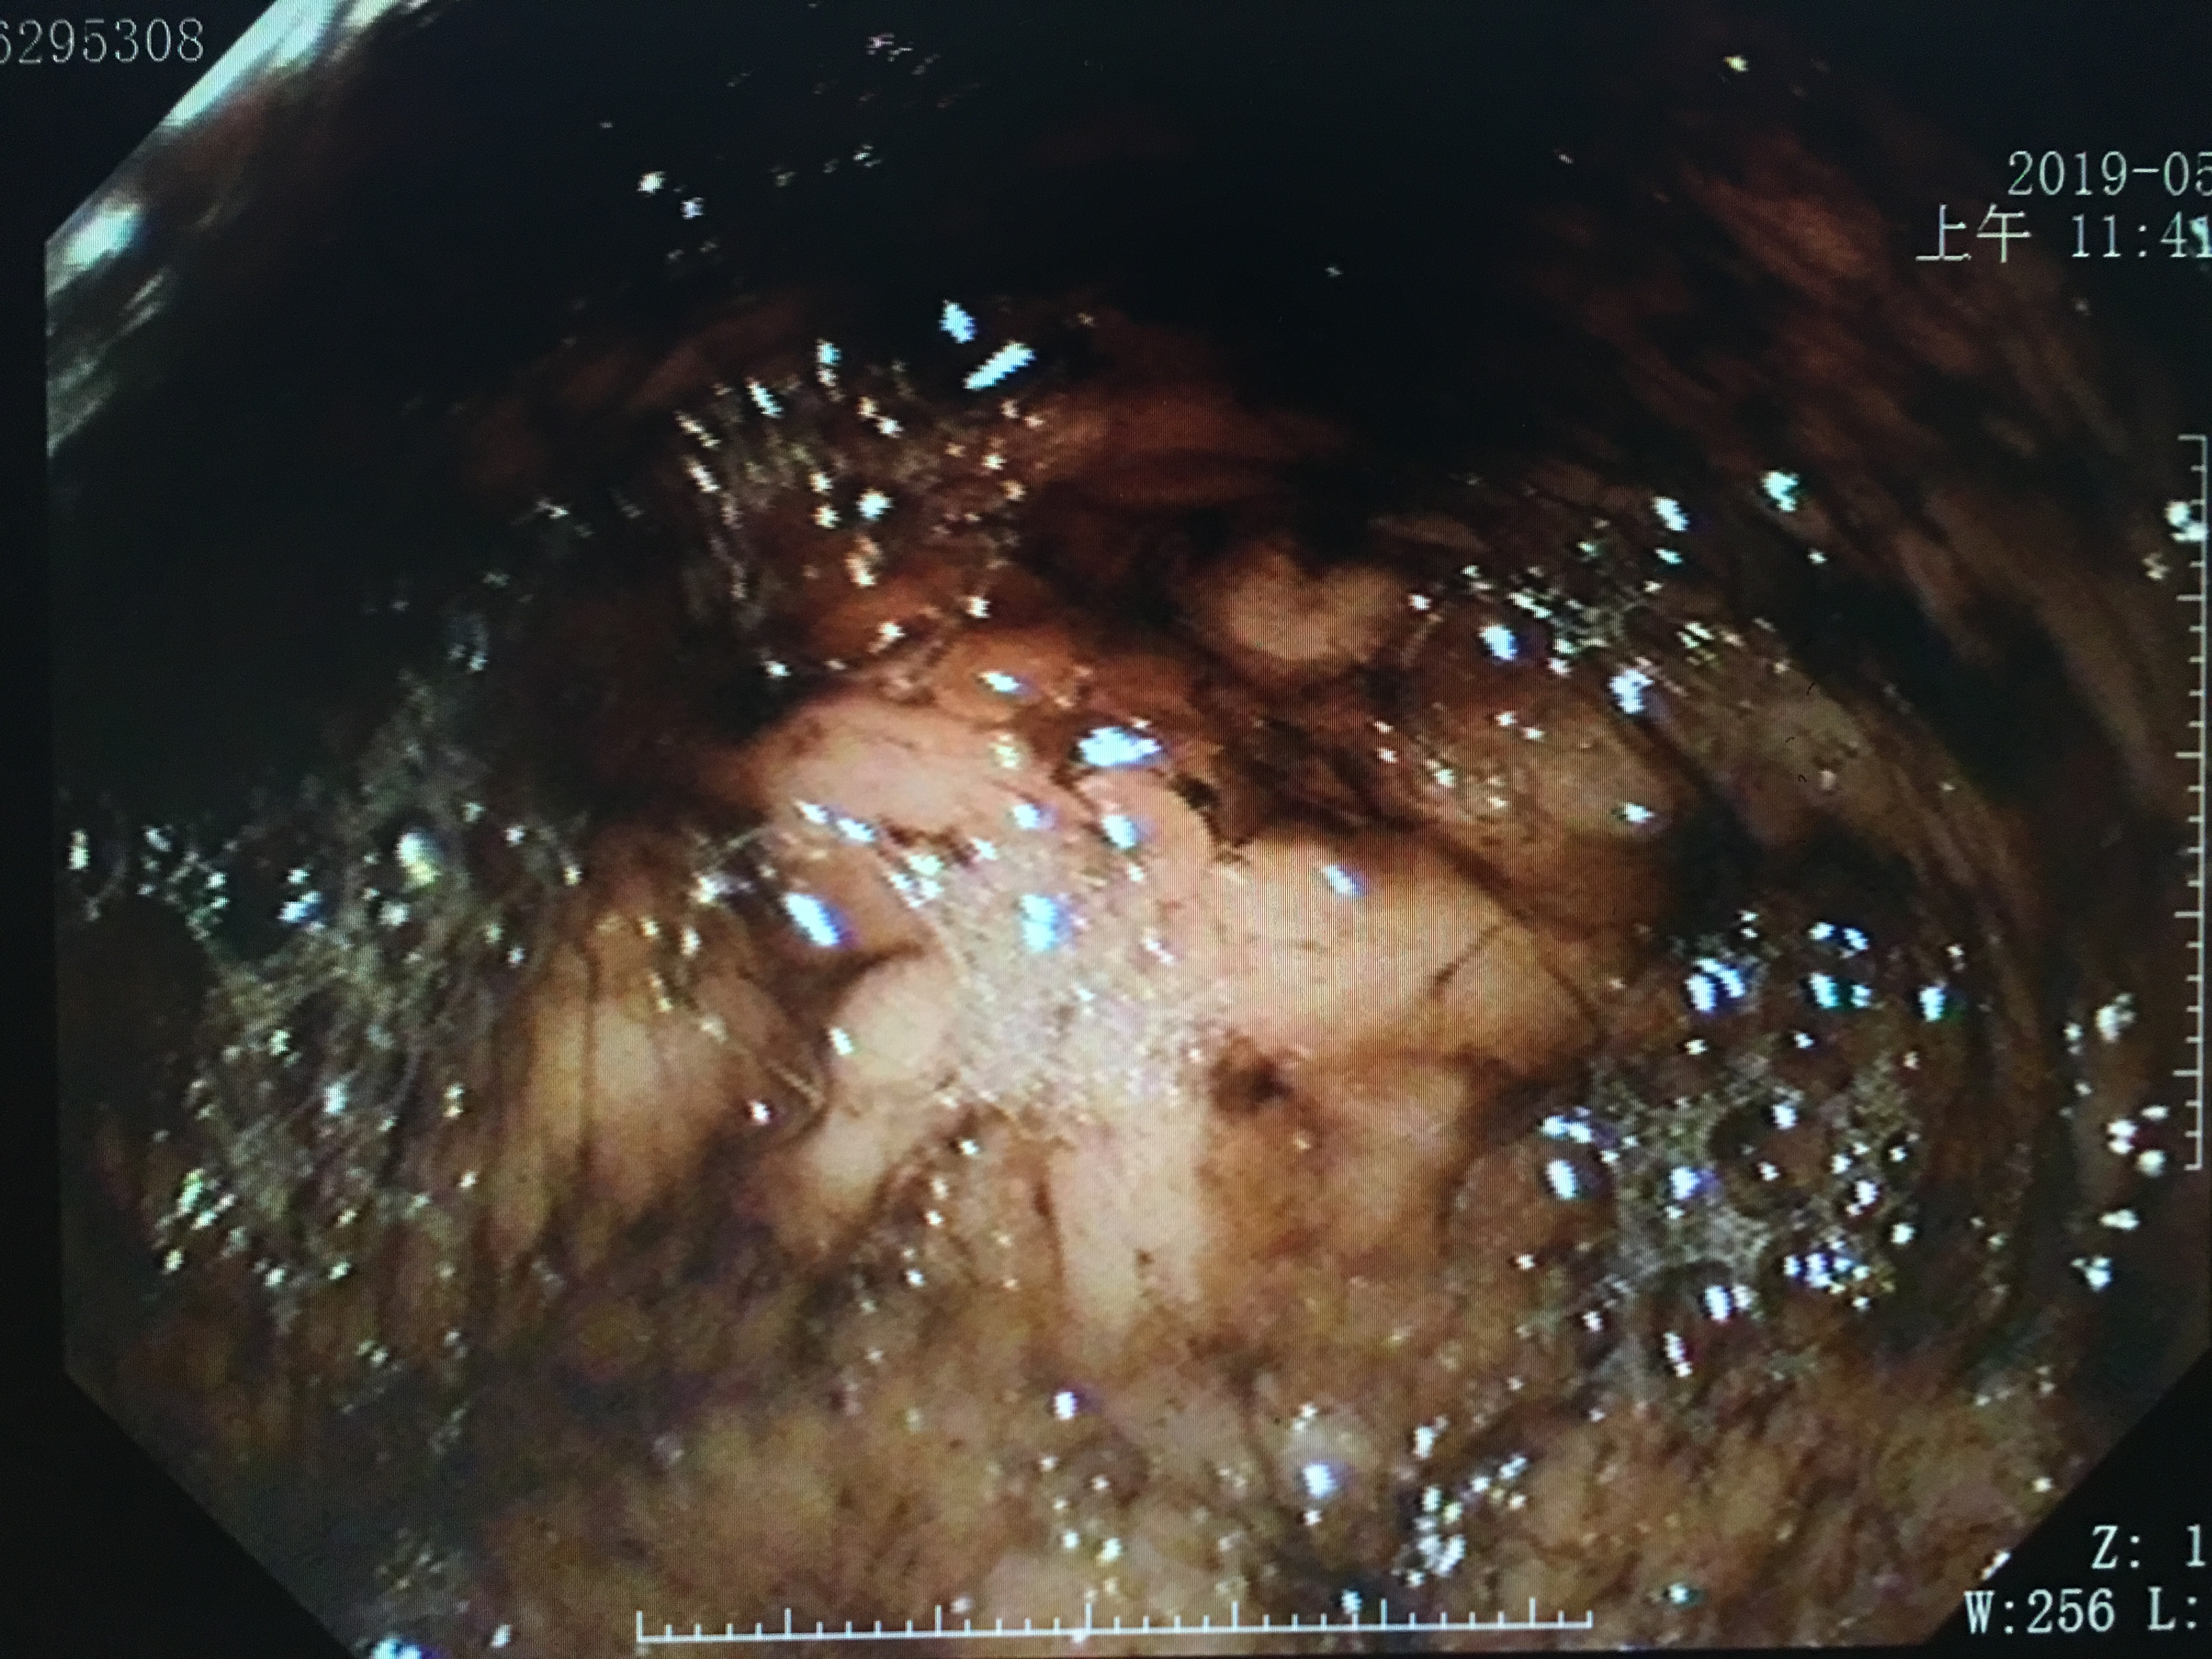

那偷吃的人做胃镜的话,会使怎么个场景?

偷吃巧克力病人的胃镜视野

如果不是十分熟练经验丰富的医生,看到这样的景象,第一反应就是“上消化道出血?”。然而,图中却是一个偷吃巧克力患者的图像。请问,这样的景象,你想要的医生看出什么端倪?

吃进去的食物,经过口腔咀嚼以及胃部蠕动消化,会覆盖在胃粘膜的表面,当胃镜伸进去的时候,看到的就是“狼藉”战场。所以,胃镜之前严格禁食是很重要的。